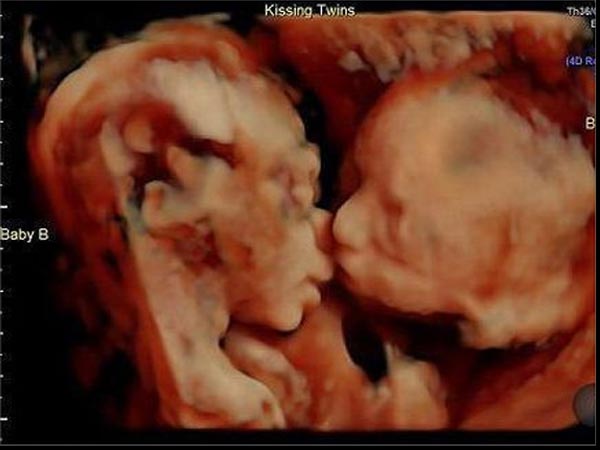

பொதுவாகவே குழந்தைகள் என்றால் அழுவார்கள். ஆனால் குழந்தைகள் கருவில் இருக்கும் போதே அழ தொடங்குகின்றன என்பது உங்களுக்கு தெரியுமா? ஆம், 4டி ஸ்கேன்களில் கவனித்தாலே இது தெரியும்.